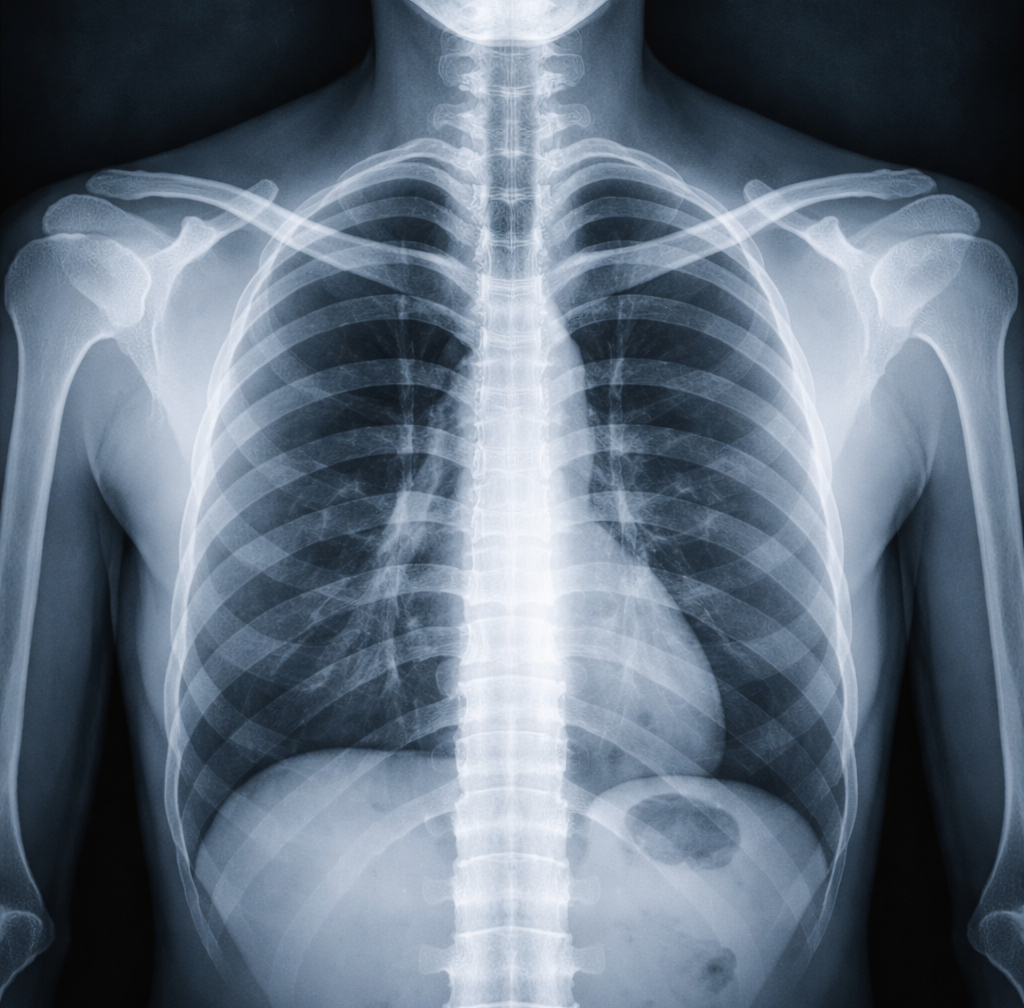

Rentgenové záření je vysíláno z rentgenového tubusu, který generuje paprsky. Tyto paprsky procházejí tělem pacienta a jsou částečně absorbovány různými tkáněmi. Tuhé materiály, jako jsou kosti, se zobrazí na rentgenovém snímku jako světlé oblasti. Naopak měkké tkáně, jako svaly nebo orgány, se zobrazí jako tmavší oblasti.

Vyšetření plic a hrudníku: Rentgen plic se používá k diagnostice onemocnění plic, jako je pneumonie, tuberkulóza nebo rakovina plic.